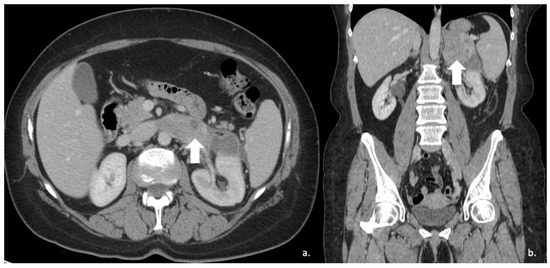

Figure 1.

60-year-old woman with adrenal adenoma. Accidental CT finding of a right adrenal mass (arrow) of approximately 3 cm, homogeneous with clear margins and density values lower than 10 HU.

Figure 2.

74-year-old male patient. Following an MRI of the digestive tract incidental finding of bilateral adrenal secondary hyperplasia. Both enlarged limbs adrenal glands > 10 mm thick with multiple nodularity hypodense on non-contrast CT (arrows).